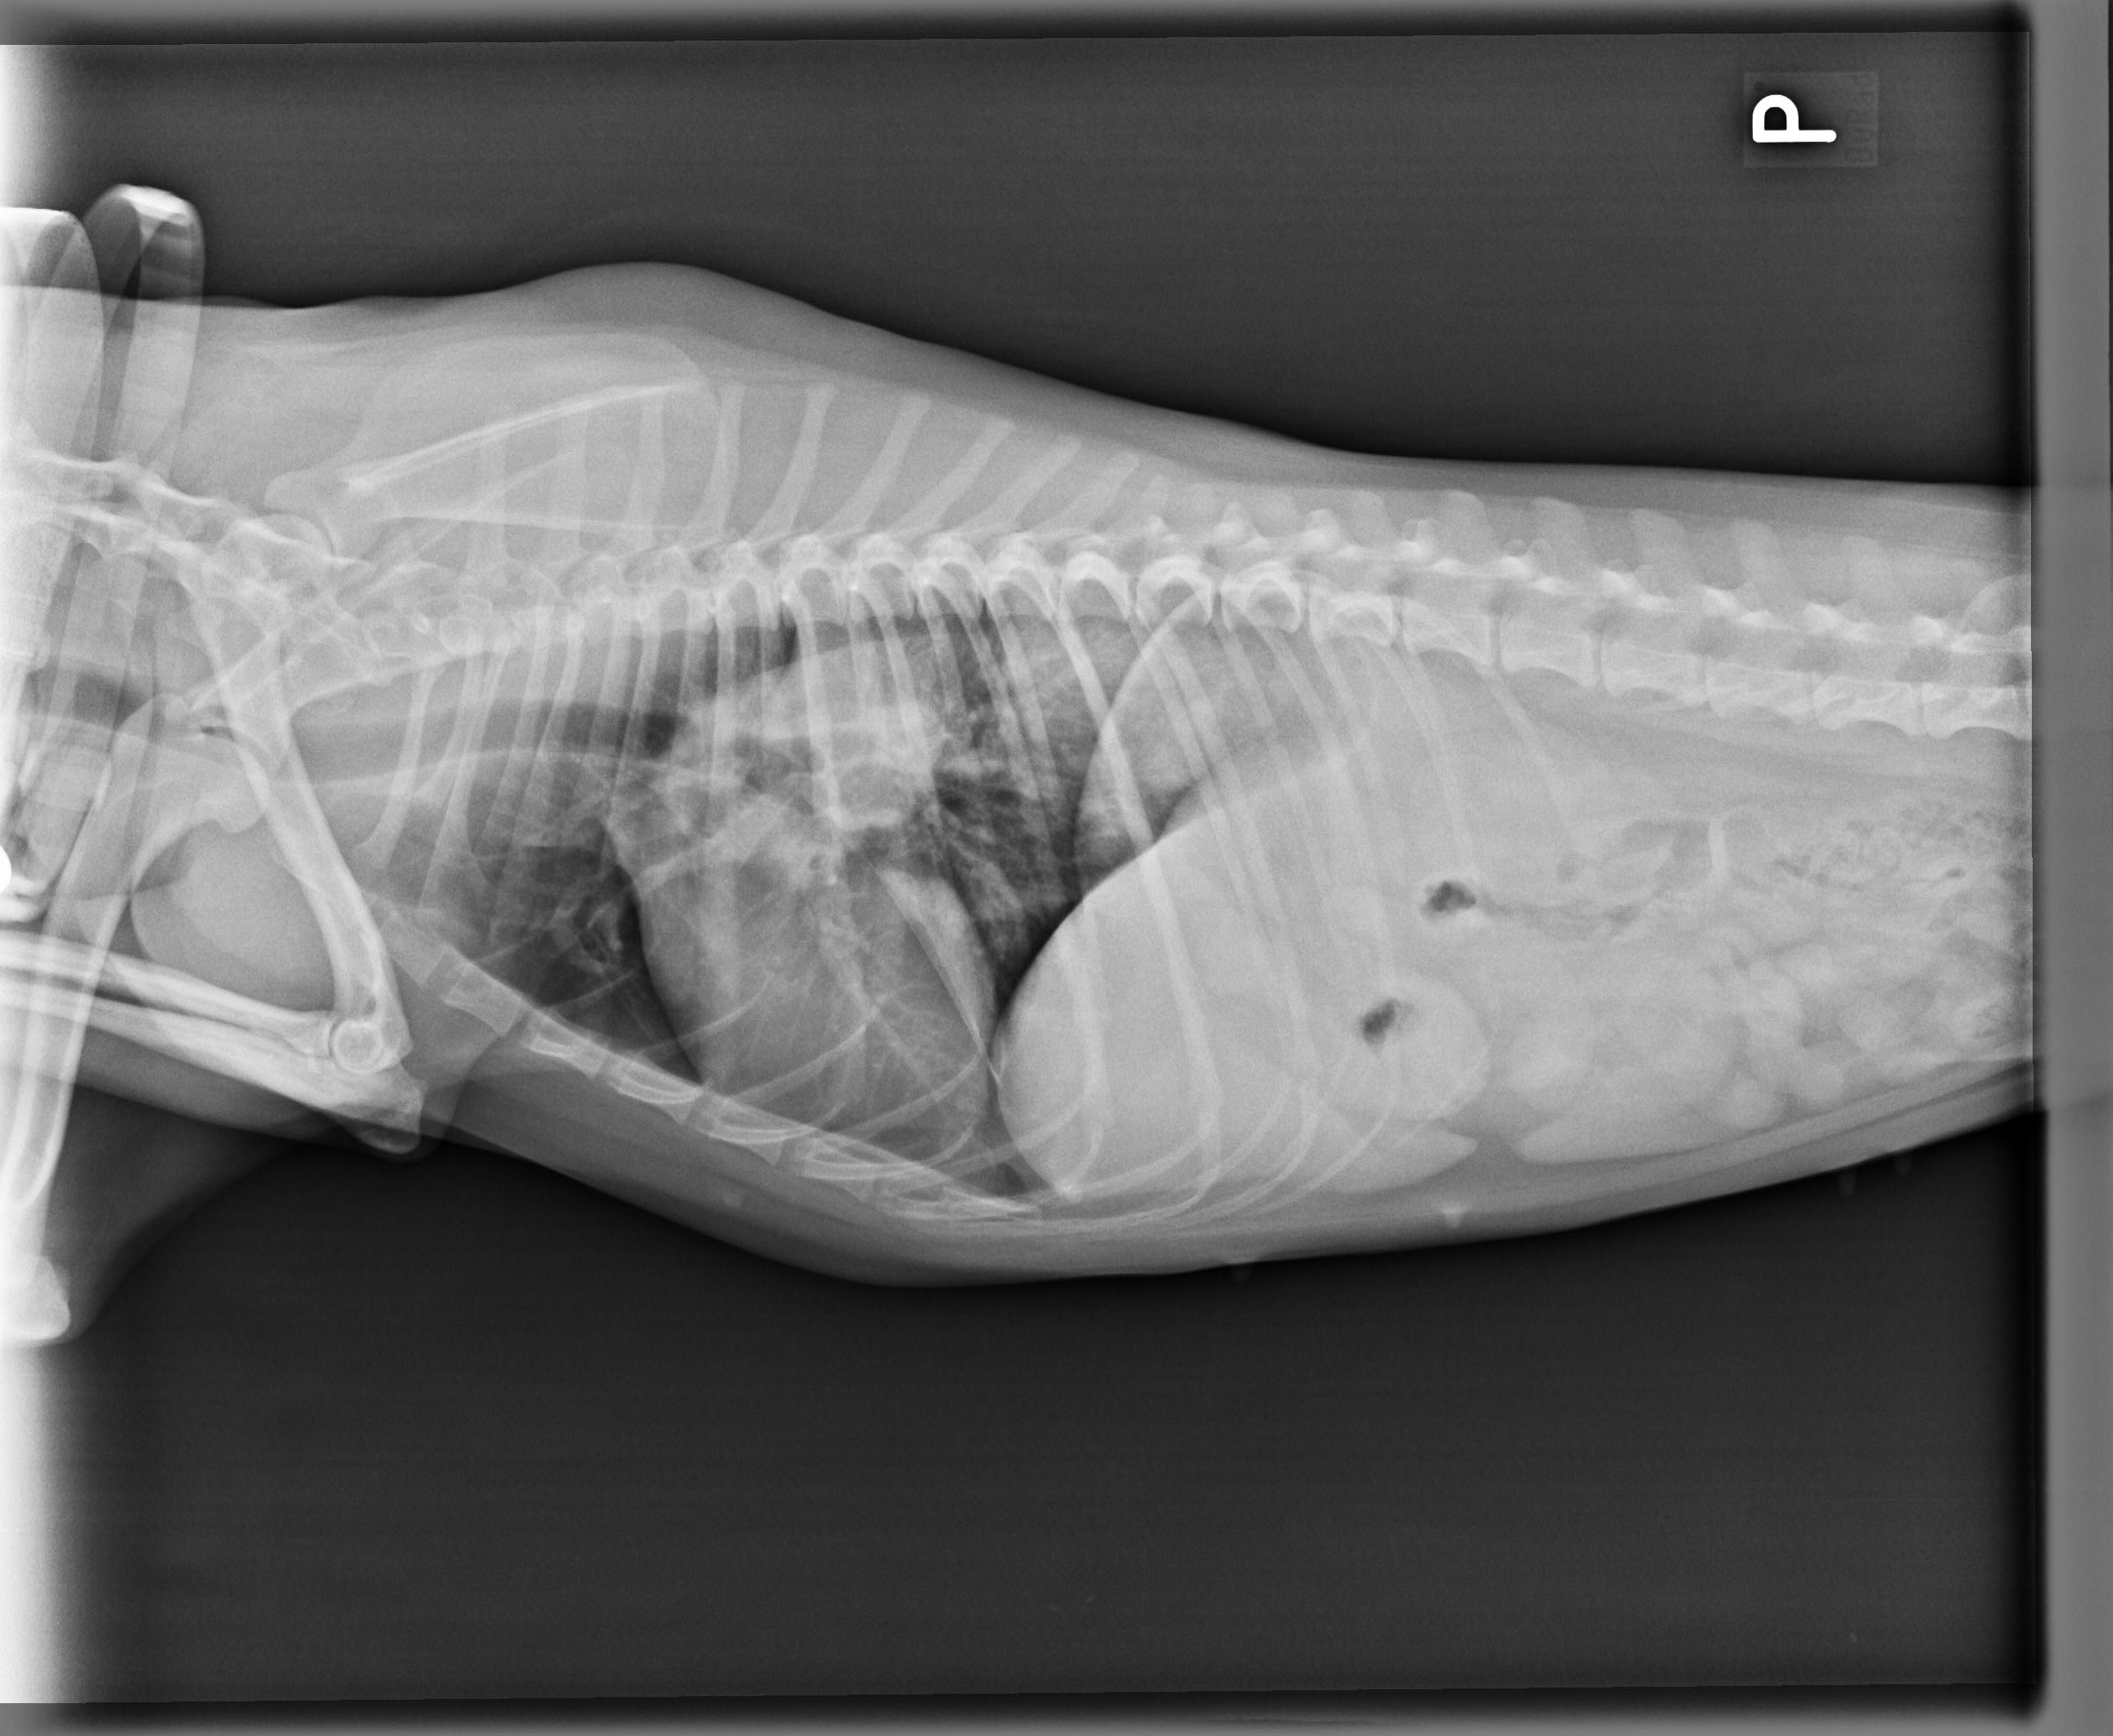

Mnoho lidí se neuvědomuje, že rakovina se týká nejen člověka, ale také našich domácích mazlíčků. Rakovina patří mezi nejčastější zabijáky psů i koček. Zde je několik příznaků, které vám napoví, že s vaším mazlíkem není něco v pořádku. Nutně to nemusí znamenat to nejhorší, je ale potřeba co nejrychleji vyhledat veterináře. Stejně jako u lidí platí – čím dříve se na nemoc přijde, tím lépe.